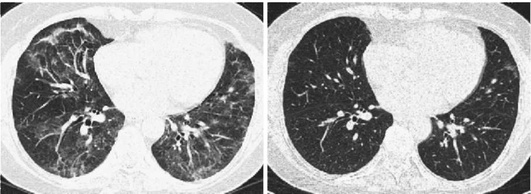

Лучевые методы исследования. Рентгенологическая картина при ЭТА зависит от стадии заболевания. В начальной фазе выявляются признаки отека интерстициальной ткани легких и распространенные мелкоочаговые затенения. При прогрессировании процесса формируются двусторонние изменения легочного рисунка по типу интерстициального фиброза, преимущественно в нижних отделах легких (рис. 2.28). В далеко зашедших случаях определяется мелко- и крупноячеистая деформация легочного рисунка. Описаны случаи, когда единственным рентгенологическим признаком болезни был односторонний плевральный выпот. Отсутствие каких-либо изменений на рентгенограммах отнюдь не исключает ЭТА. Так, при бериллиозе у 23-59% больных может выявляться умеренно выраженная двусторонняя лимфоаденопатия, а в ряде случаев - рентгенотрицательная форма бериллиоза (Dweik R.A., 2015). У 30% из 71 больных ЭТА, наблюдавшихся нами в клинике пульмонологии, в момент обследования изменений на рентгенограммах не было (Орлова Г.П., 2019). Группа больных ЭТА была обозначена условно как рентгенотрицательная группа. Уточнить диагноз помогает КТ легких, выявляющая интерстициальные изменения в легочной ткани по типу «матового стекла», усиление и деформацию легочного и сосудистого рисунка (рис. 2.29), фиброзные изменения тяжистого и звездчатого типов, на поздних стадиях - «сотовое легкое». ВРКТ выявляет «матовое стекло» и другие изменения в легочной паренхиме, которые не видны при обычном рентгенологическом исследовании. Но даже ВРКТ не всегда выявляет изменения в легочной ткани. Так, в 25% случаев гистологически подтвержденного хронического берил-лиоза легких ВРКТ была нормальной (Dweik R.A., 2013; Амосов В.И., Сперанская А.А., 2015; Amanullah S. et al., 2015).

Проведенное нами динамическое исследование КТ-паттернов у 42 больных ЭТА показало трансформацию отдельных типов интерстициальных пневмоний по мере прогрессирования патологического процесса в фиброзную НСИП или ОИП (рис. 2.30), что подтверждает объединительную концепцию интерстициальных пневмоний вне зависимости от этиологического фактора, которые являются не отдельными нозологическими формами, а стадиями течения фиброзирующего процесса в легких (Илькович М.М., Новикова Л.Н., 2018; Орлова Г.П. и др., 2019).